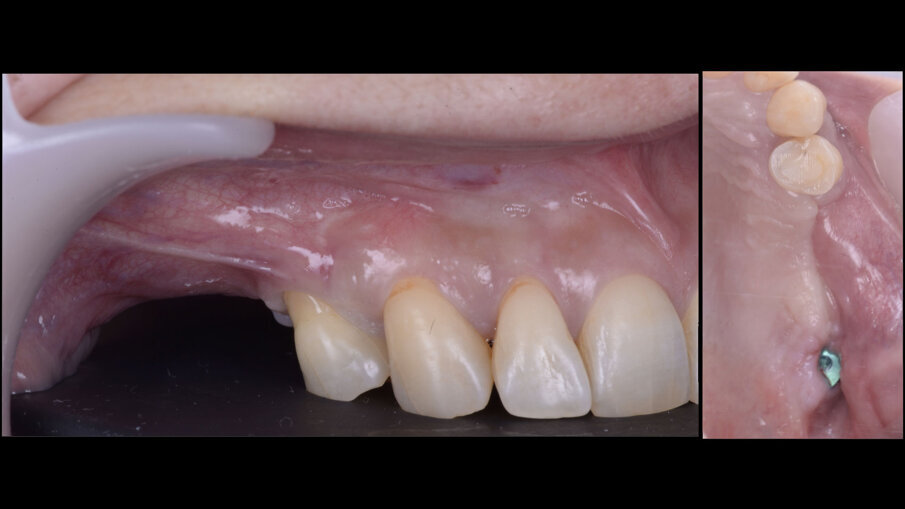

A distanza di 3 mesi, si procede alla seconda fase implantare abbinata a una vestiboloplastica, col fine di ripristinare la profondità del fornice vestibolare ed un’idonea anatomia dei tessuti molli perimplantari (Figg. 14, 15). Le biopsie del tessuto osseo prelevate in fase di inserimento implantare sono state processate con tecnica standard, non decalcificata, e colorate con blu di toluidina e pironina gialla.

A 9 mesi dalla chirurgia ricostruttiva, si riscontra una buona stabilità dei tessuti duri e molli perimplantari (Figg. 16, 17). All’esame istologico descrittivo (Fig. 18) si riscontrano granuli residui del biomateriale utilizzato per la rigenerazione, a stretto contatto col tessuto osso neoformato. Cellule simil-osteoblastiche sembrano allineate lungo il fronte di rigenerazione ossea. Gli spazi midollari appaiono ricchi di vasi e privi di infiltrato infiammatorio.

Fig. 14 - Incisione palatale a spessore parziale finalizzata alla seconda fase implantare con vestiboloplastica.

Fig. 15 - Sutura della seconda fase implantare con vestiboloplastica.

Fig. 16 - Guarigione clinica a 6 settimane.